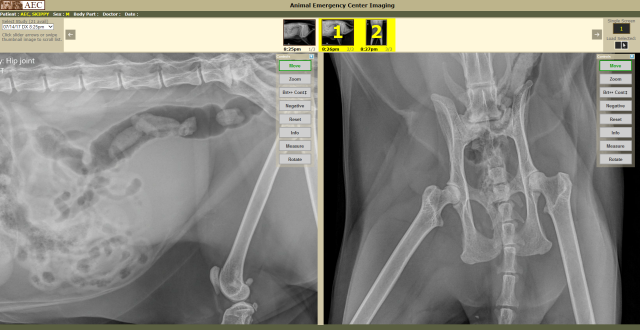

Here is a sample split screen view:

Clicking on the Split Screen "1|2" button will divide the screen into two usable viewing panels. If a study contains 2 images, both images will automatically load.